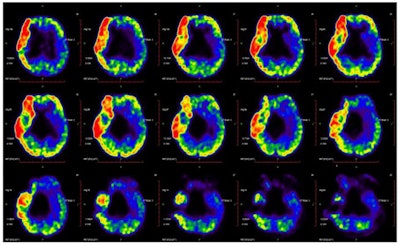

Images of F-18 FDG cerebral glucose metabolism were acquired (Biograph mCT 64, Siemens Healthineers) with children placed supine on the scan table after sedation. The scans lasted for 45 minutes. Concentrations of F-18 FDG radiotracer were calculated using mean standardized uptake value (SUVmean), with results visually evaluated by two experienced nuclear medicine physicians.

In the individual analysis, most patients showed left > right asymmetry of glucose metabolism in the central region, cerebellum, frontal lobe, and parietal lobe. Glucose metabolism in these left regions was significantly higher than those of the corresponding regions in the right hemisphere, according to the findings.

The dataset as a whole revealed that the left cerebellum showed higher metabolic activity than the right in most patients (83.8%), with levels of metabolic activity also negatively correlated with GMFCS scores (Spearman's r = -0.47, p = 0.01), the group reported.